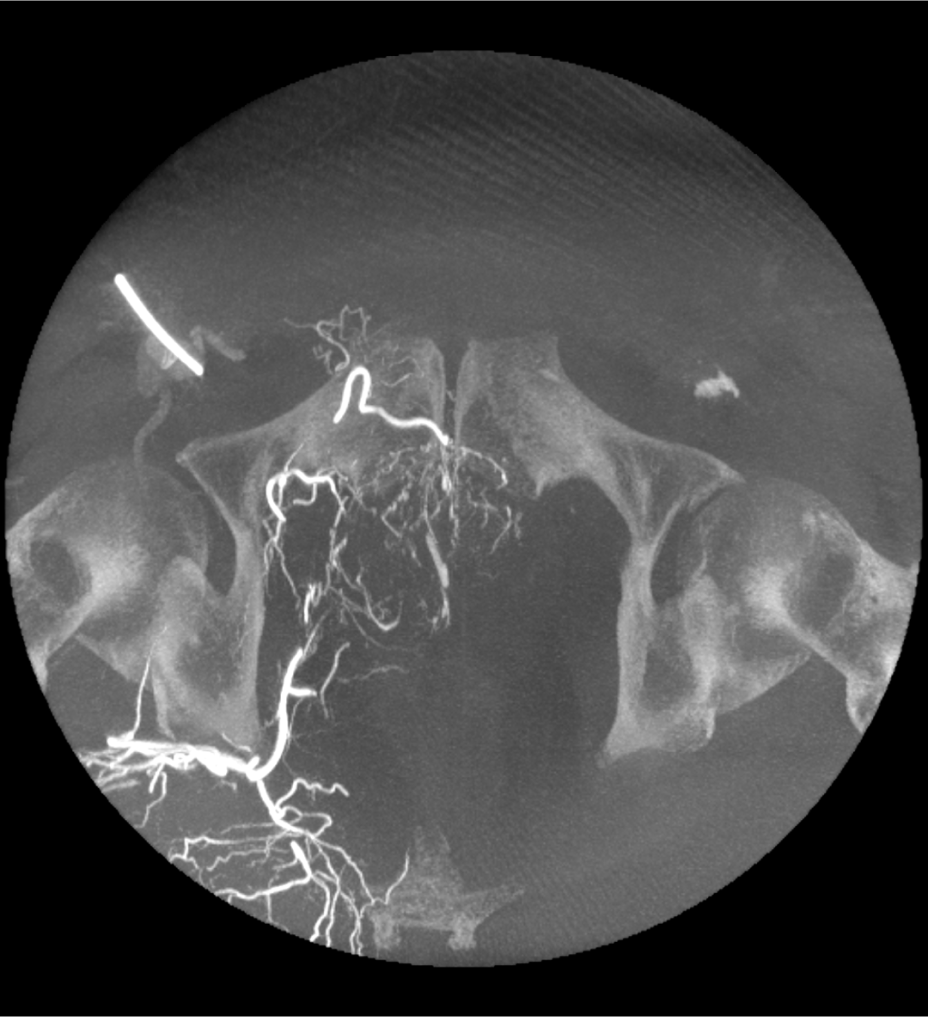

• Angiographie par résonance magnétique (CE-MRA)